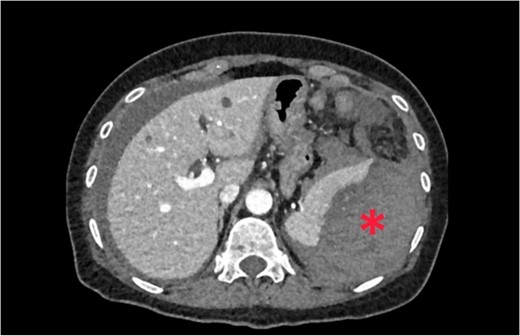

A 62-year-old woman admitted at the emergency department complaining of abdominal pain with sudden-onset 6 h ago. On arrival, there was a collapse, with a blood pressure of 80/60 mmHg and a pulse of 120/min. She was pale, apyretic, and had with signs of peritoneal irritation. The hemoglobin was at 7.3 g/dl. After resuscitation measures and transfusion of 2 units of red blood cells transfusions, contrast enhanced CT was performed. CT showed free fluid in the abdomen and a large perisplenic hematoma (Fig. 6). As the patient remained haemodynamically unstable, she underwent an exploratory laparotomy. During laparotomy, there was a hemoperitoneum related to complete decapsulation of spleen. Splenectomy was performed. Histological examination confirmed the non-pathological aspect of a decapsulated spleen. The patient’s hospital course was uncomplicated. She was discharged on the seventh post-operative day.